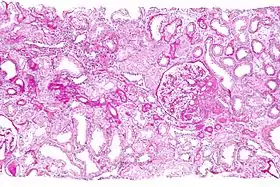

![]() صورة مجهرية لخزعة كلوية. | |